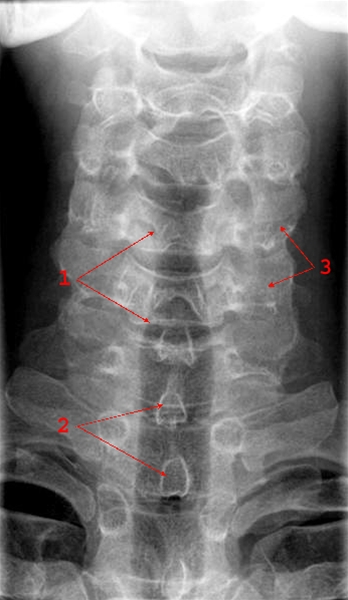

Normalt frontalbillede af cervikalcolumna (rygsøjlen, nakke).

1. Trachea (luftrør)

2. Processus spinosus (torntap)

3. Processus transversi (tværtappe)